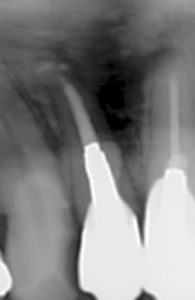

【4年後のレントゲン写真 パーフォレーション部の骨再生が見られる】

【11年後のレントゲン写真 再発もなく予後は良好】